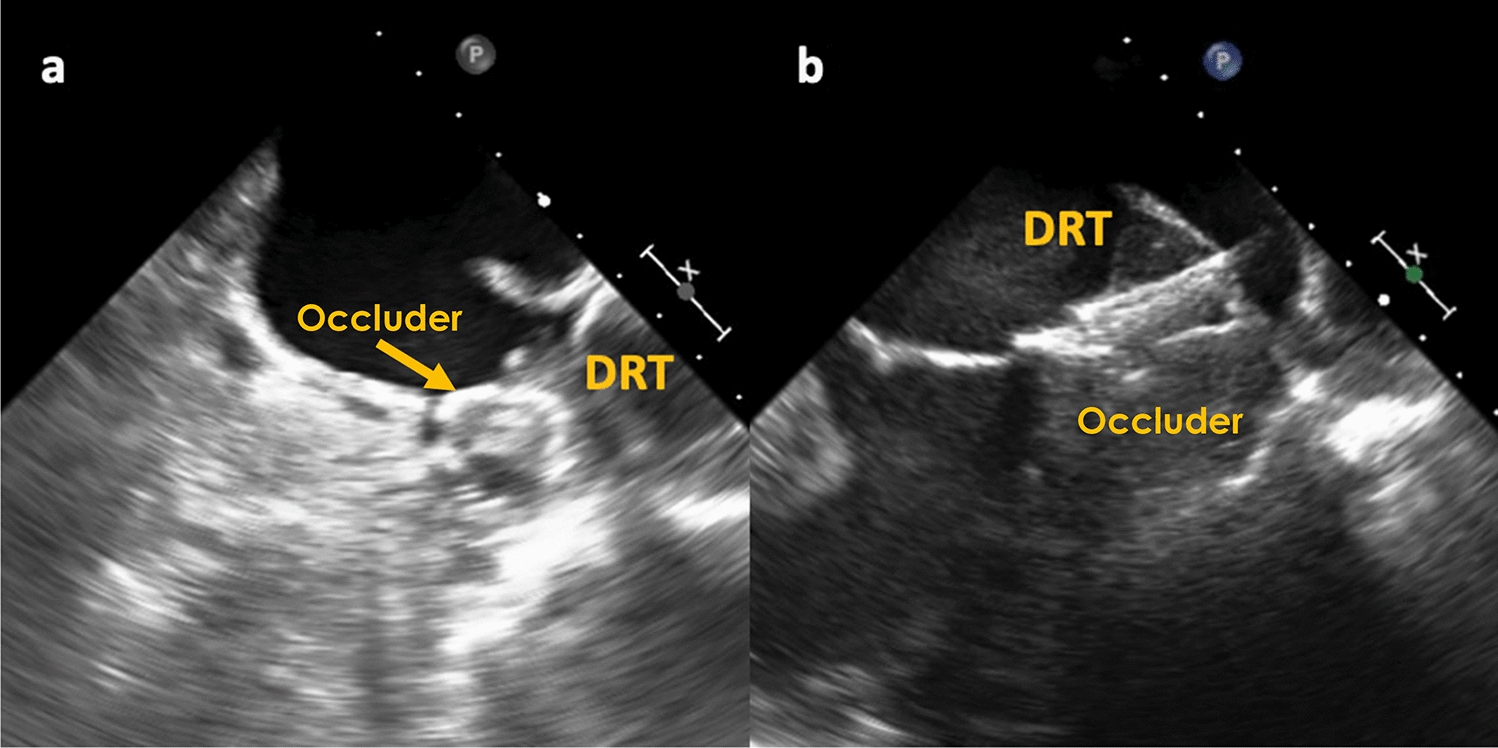

With regards to DRT, characteristics and its impact on stroke/SE, DRT were mainly located centrally on the occluder (47.3%) or along the LUPV ridge transition zone (41.9%) (Fig. 2). The remaining DRT were found on the occluder at the mitral valve side (10.9%). No difference was seen between symptomatic and non-symptomatic patients in regard to DRT position on the occluder (p = 0.64). DRT size measured vertically and horizontally were numerically larger in symptomatic DRT patients but missed significance (p = 0.22 and = 0.51, respectively).

Fig. 2

Position of DRT on LAAC occluder, a valvular DRT position; b DRT in a central occluder position, a.e. attached to screw, c DRT located on the ridge side of occluder in a “cul-de-sac” between LUPV and occluder